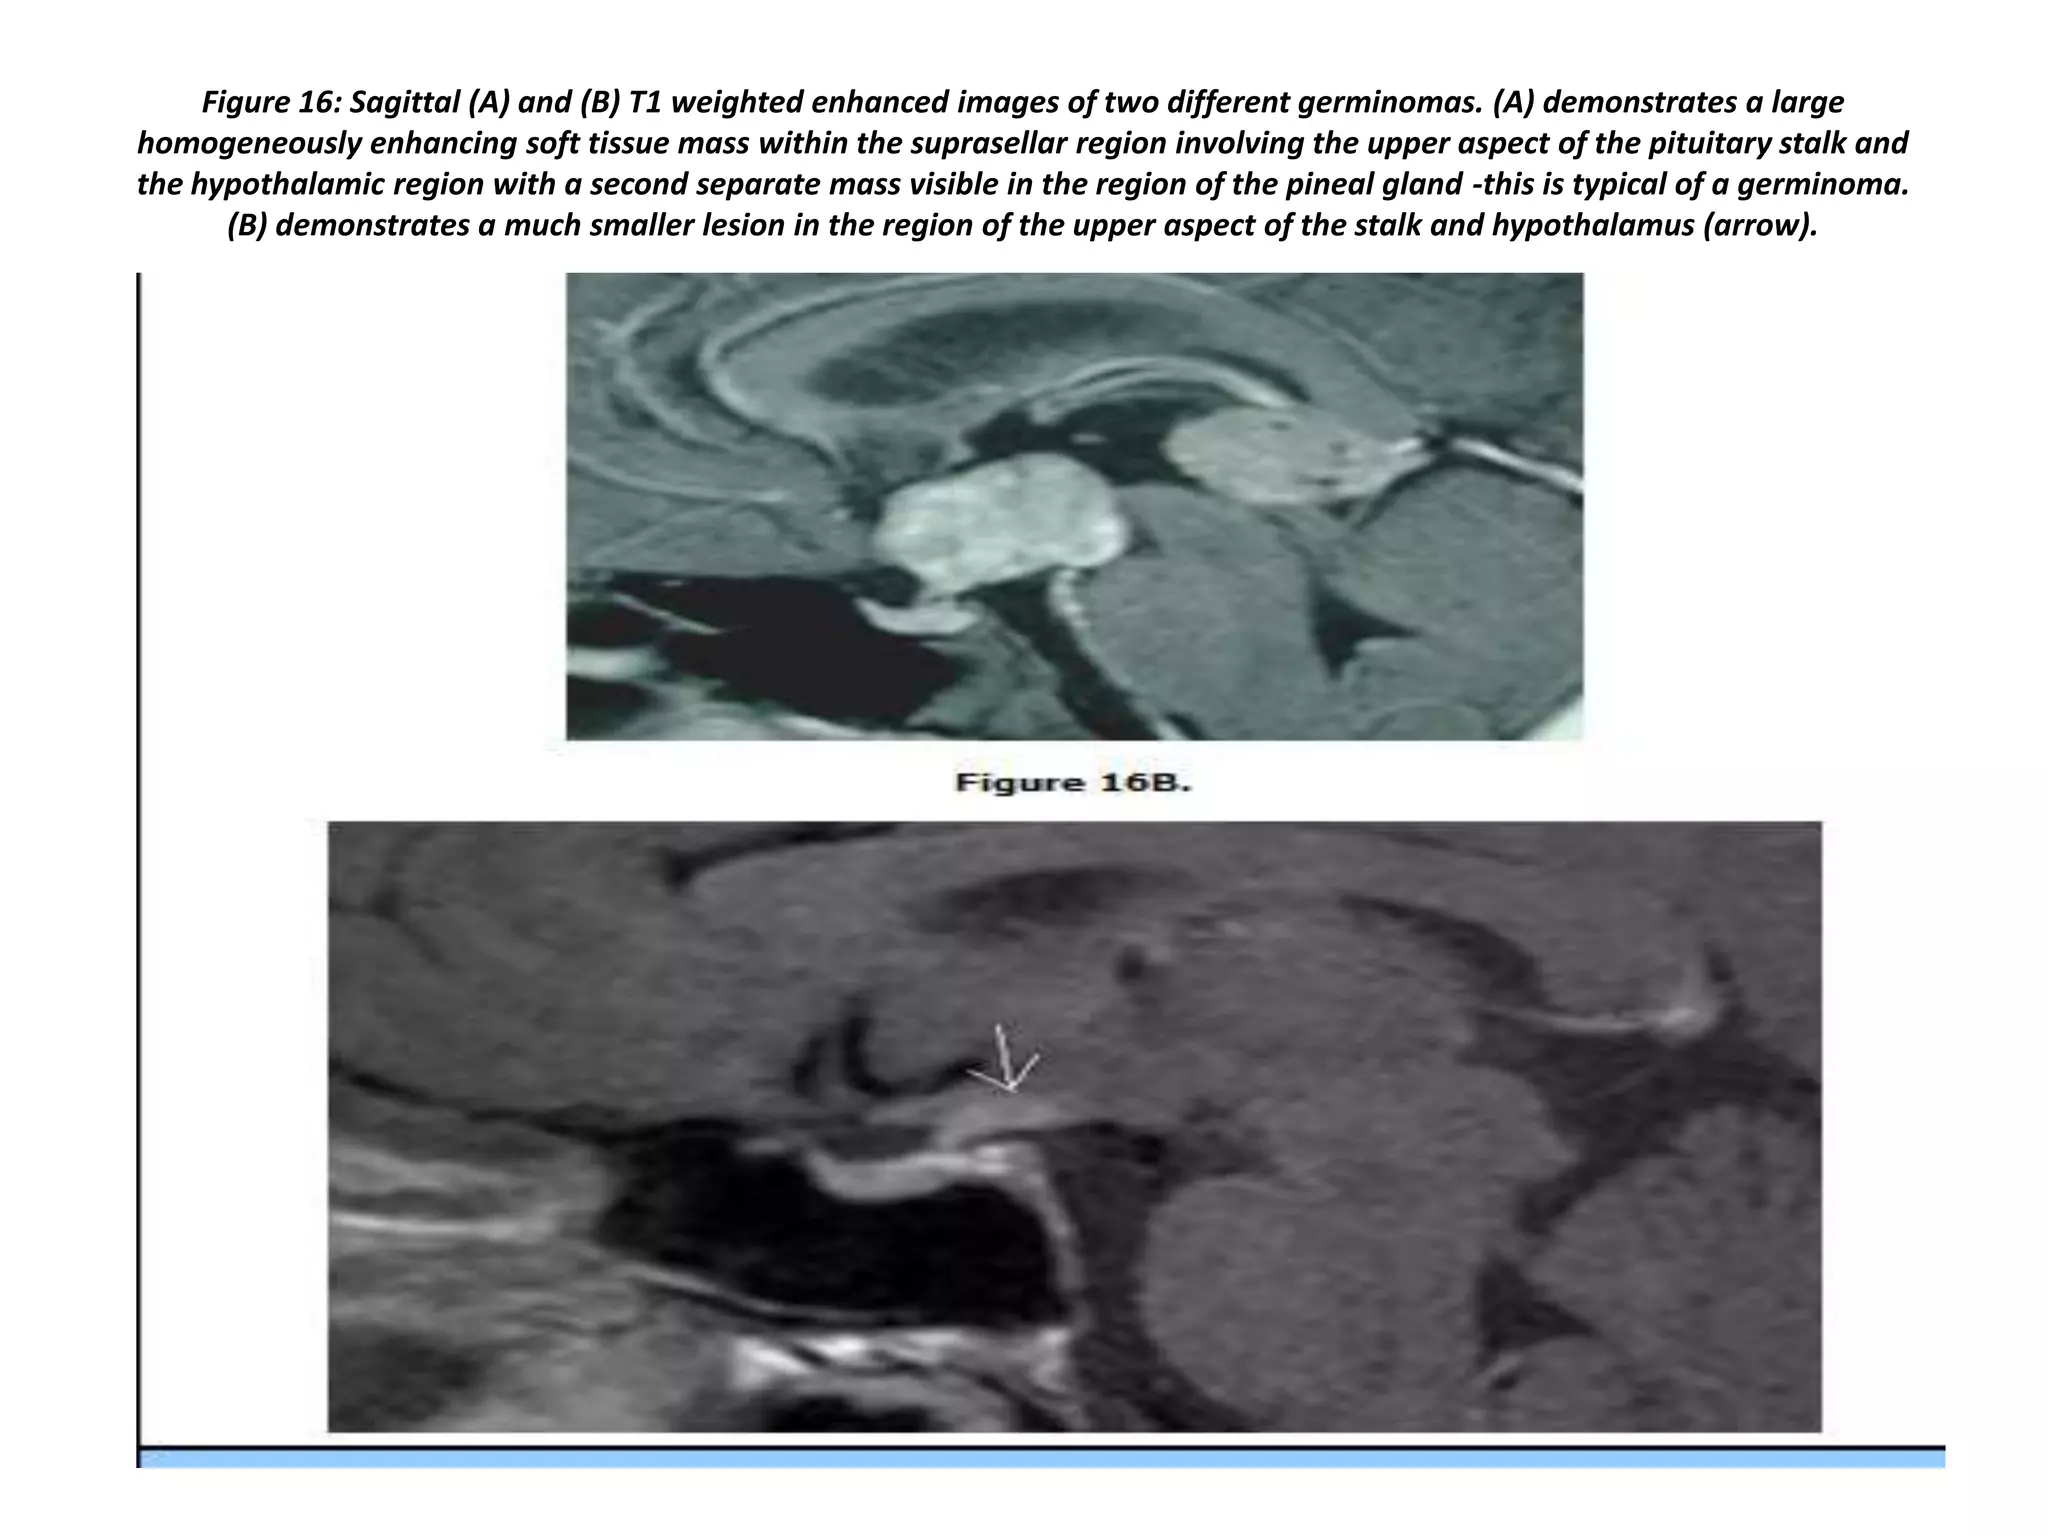

Figure 16: Sagittal (A) and (B) T1 weighted enhanced images of two different germinomas. (A) demonstrates a large

homogeneously enhancing soft tissue mass within the suprasellar region involving the upper aspect of the pituitary stalk and

the hypothalamic region with a second separate mass visible in the region of the pineal gland -this is typical of a germinoma.

(B) demonstrates a much smaller lesion in the region of the upper aspect of the stalk and hypothalamus (arrow).

Figure 16: Sagittal(A) and (B) T1 weighted enhanced images of two different germinomas. (A) demonstrates a large homogeneously enhancing soft tissue mass within the suprasellar region involving the upper aspect of the pituitary stalk and the hypothalamic region with a second separate mass visible in the region of the pineal gland -this is typical of a germinoma. (B) demonstrates a much smaller lesion in the region of the upper aspect of the stalk and hypothalamus (arrow).